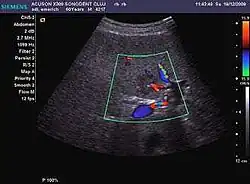

The ultrasound appearance is a well defined lesion, with very thin, almost unapparent walls, without circulatory signal at Doppler or CEUS investigation. The content is transonic suggesting fluid composition. The presence of membranes, abundant sediment or cysts inside is suggestive for parasitic, hydatid nature. Posterior from the lesion the acoustic enhancement phenomenon is seen, which strengthens the suspicion of fluid mass. They typically displace normal liver vessels but no vascular or biliary invasion occurs.

-

Liver cyst -

Hydatid liver cyst. Diagnostic criteria are the presence of membranes and sediment inside.